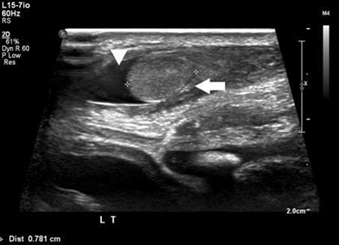

During the period under review, a total of 69 patients with 46 xy dsd were evaluated. Twelve (20.3%) patients, were diagnosed to have 5-α-reductase deficiency, based on hormonal investigations, the (dht/t) ratio, post-hcg stimulation, was high in all patients. Their ages ranged from birth to 12 years. The diagnostic imagings (ultrasound and/or magnetic resonance mr) were utilized to elucidate the internal organs (figures 2 and 3). None of the patients were found to have internal female structures. However all were found to have testes in variable positions (abdomen, inguinal canal and scrotum).

Establishing the diagnosis of 5-α-reductase deficiency is often suggested by an elevated plasma testosterone (t), to dihydrotestosterone (dht) ratio following human chorionic gonadotropin hormone (hcg) stimulation8-10. Genetic studies can confirm the diagnosis11-16. Imaging diagnostic studies with ultrasonography (us) and/or magnetic resonance (mr) will help in elucidating the internal structures. In all patients no female internal organs were demonstrated, however, all were found to have testes in variable positions (abdomen, inguinal canal and scrotum)17-24.